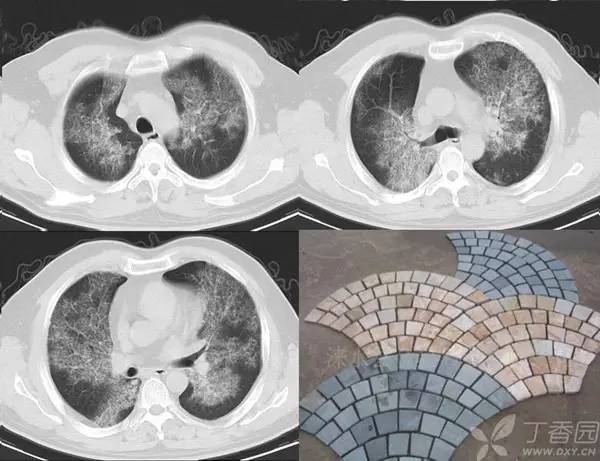

碎石路征或称铺路石征,是胸部 CT 上的一种影像学征象,主要表现为在弥漫性或散在分布的毛玻璃样浸润影中,有小叶间隔增厚、小叶内线状影重叠存在。

碎石路征最初在肺泡蛋白沉积症(PAP)的病例中发现,并认为是 PAP 特征性的胸部 CT 表现;但实际上,感染性疾病、肿瘤、特发性肺弥漫性疾病(DPLD)、吸人性病变等都也可以出现。